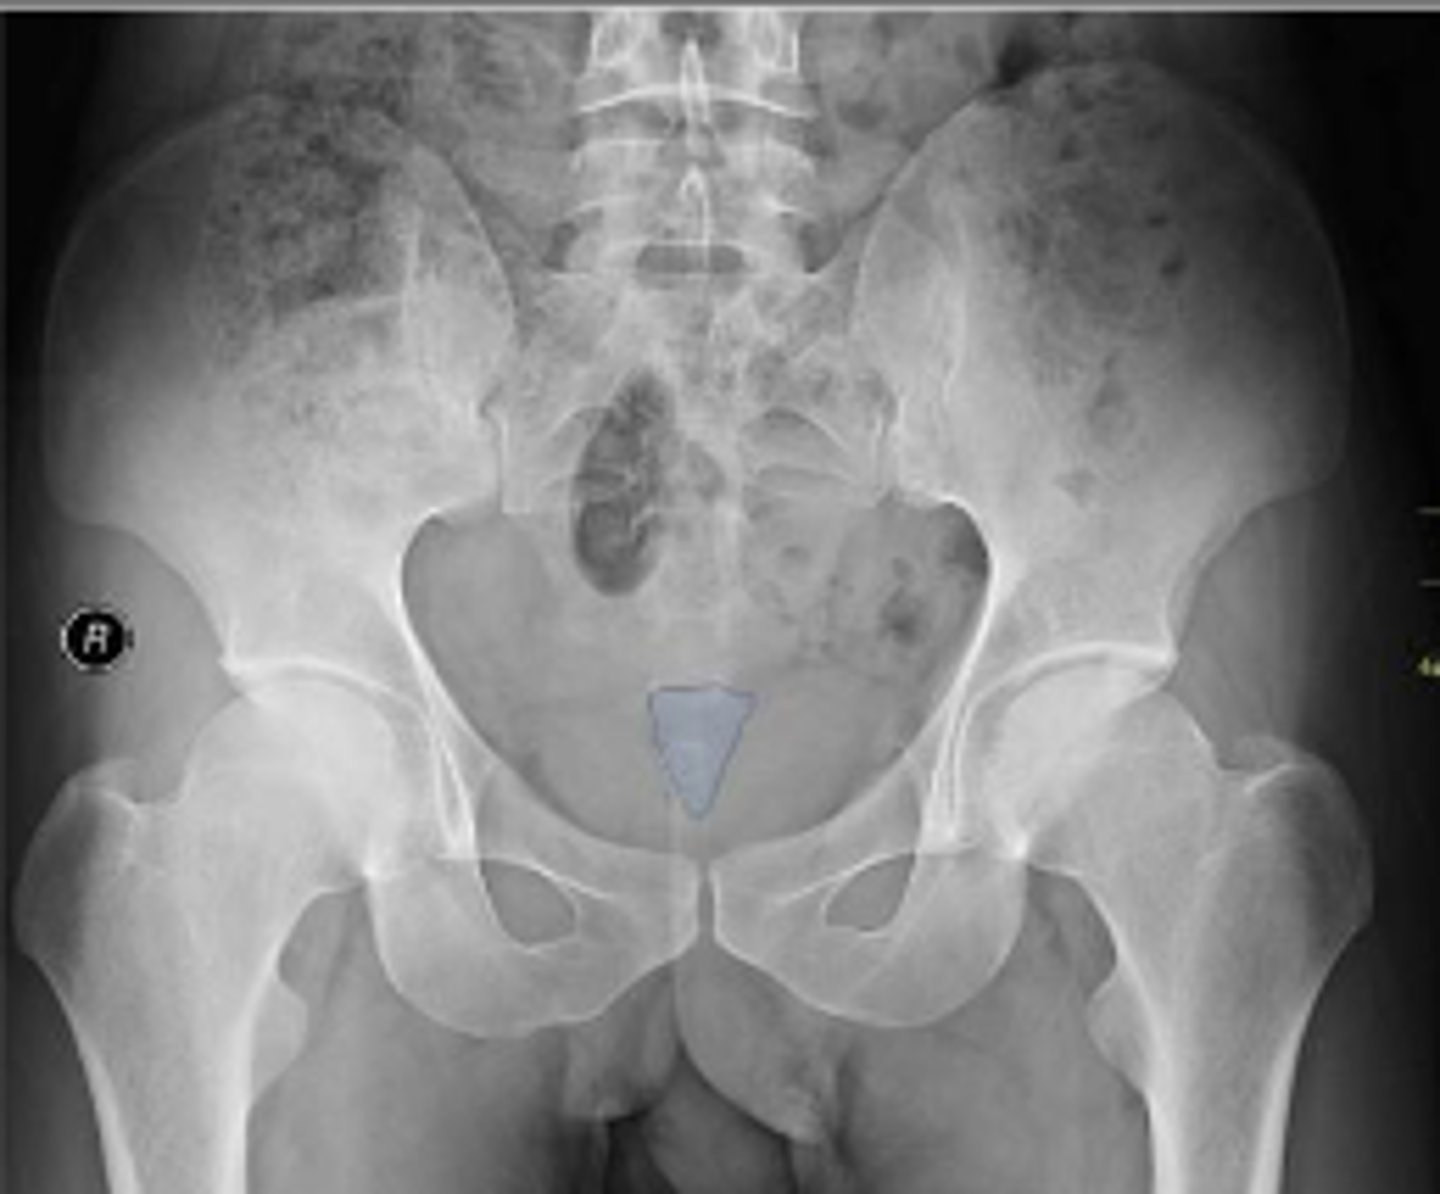

Bilateral frog leg view

What is the name of the radiographic view?

Phleboliths

What are the arrows pointing to?

Right ischial spine

Posterior rim of the right acetabulum

Anterior rim of the right acetabulum

Right sacroiliac joint space

What joint space is the arrow pointing to?

Lesser trochanter of the right femur

Greater trochanter of the right femur

Right posterior inferior iliac spine

Intertrochanteric line of the right femur

Right ischial tuberosity